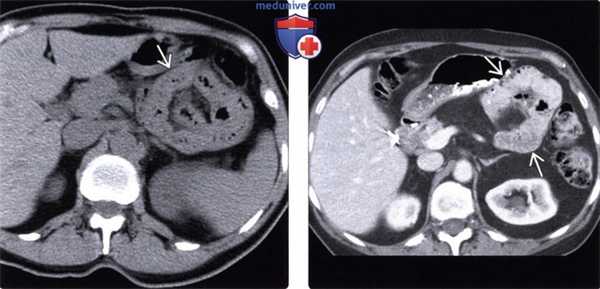

(Слева) На аксиальной нативной КТ определяется группа «инкапсулированных» петель тонкой кишки в левой половине брюшной полости. Обратите внимание на локализацию этих петель, тесно прилежащих к дистальным отделам двенадцатиперстной кишки, задней стенке желудка и ободочной кишке - в полном соответствии с местоположением парадуоденальной грыжи.

(Справа) На аксиальной КТ с контрастным усилением визуализируется группа незначительно расширенных петель тонкой кишки S3 в левом верхнем квадранте, смещающих желудок кпереди. Брыжеечные сосуды, кровоснабжающие участки кишки, выпавшие в грыжу, сходятся в центре (группы петель кишечника).

(Слева) На аксиальной КТ с контрастным усилением определяется овоидной формы группа петель тощей кишки в верхнем левом квадранте. Обратите внимание на четко очерченные края грыжевого мешка вокруг выпавшей кишки, а также на брыжеечные сосуды, сходящиеся к центру мешка. Данные изменения типичны для левосторонней пара-дуоденальной грыжи.

(Справа) На отсроченной рентгенограмме верхних отделов ЖКТ у этого же пациента определяется группа плотно прилегающих друг к другу расширенных петель тощей кишки и замедление прохождения контраста в нерасширенные дистальные отделы тонкой кишки.